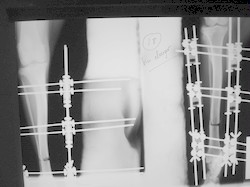

PRÁCTICAS CURSO DE FIJACIÓN EXTERNA PERFECCIONAMIENTO.

Elongacion.